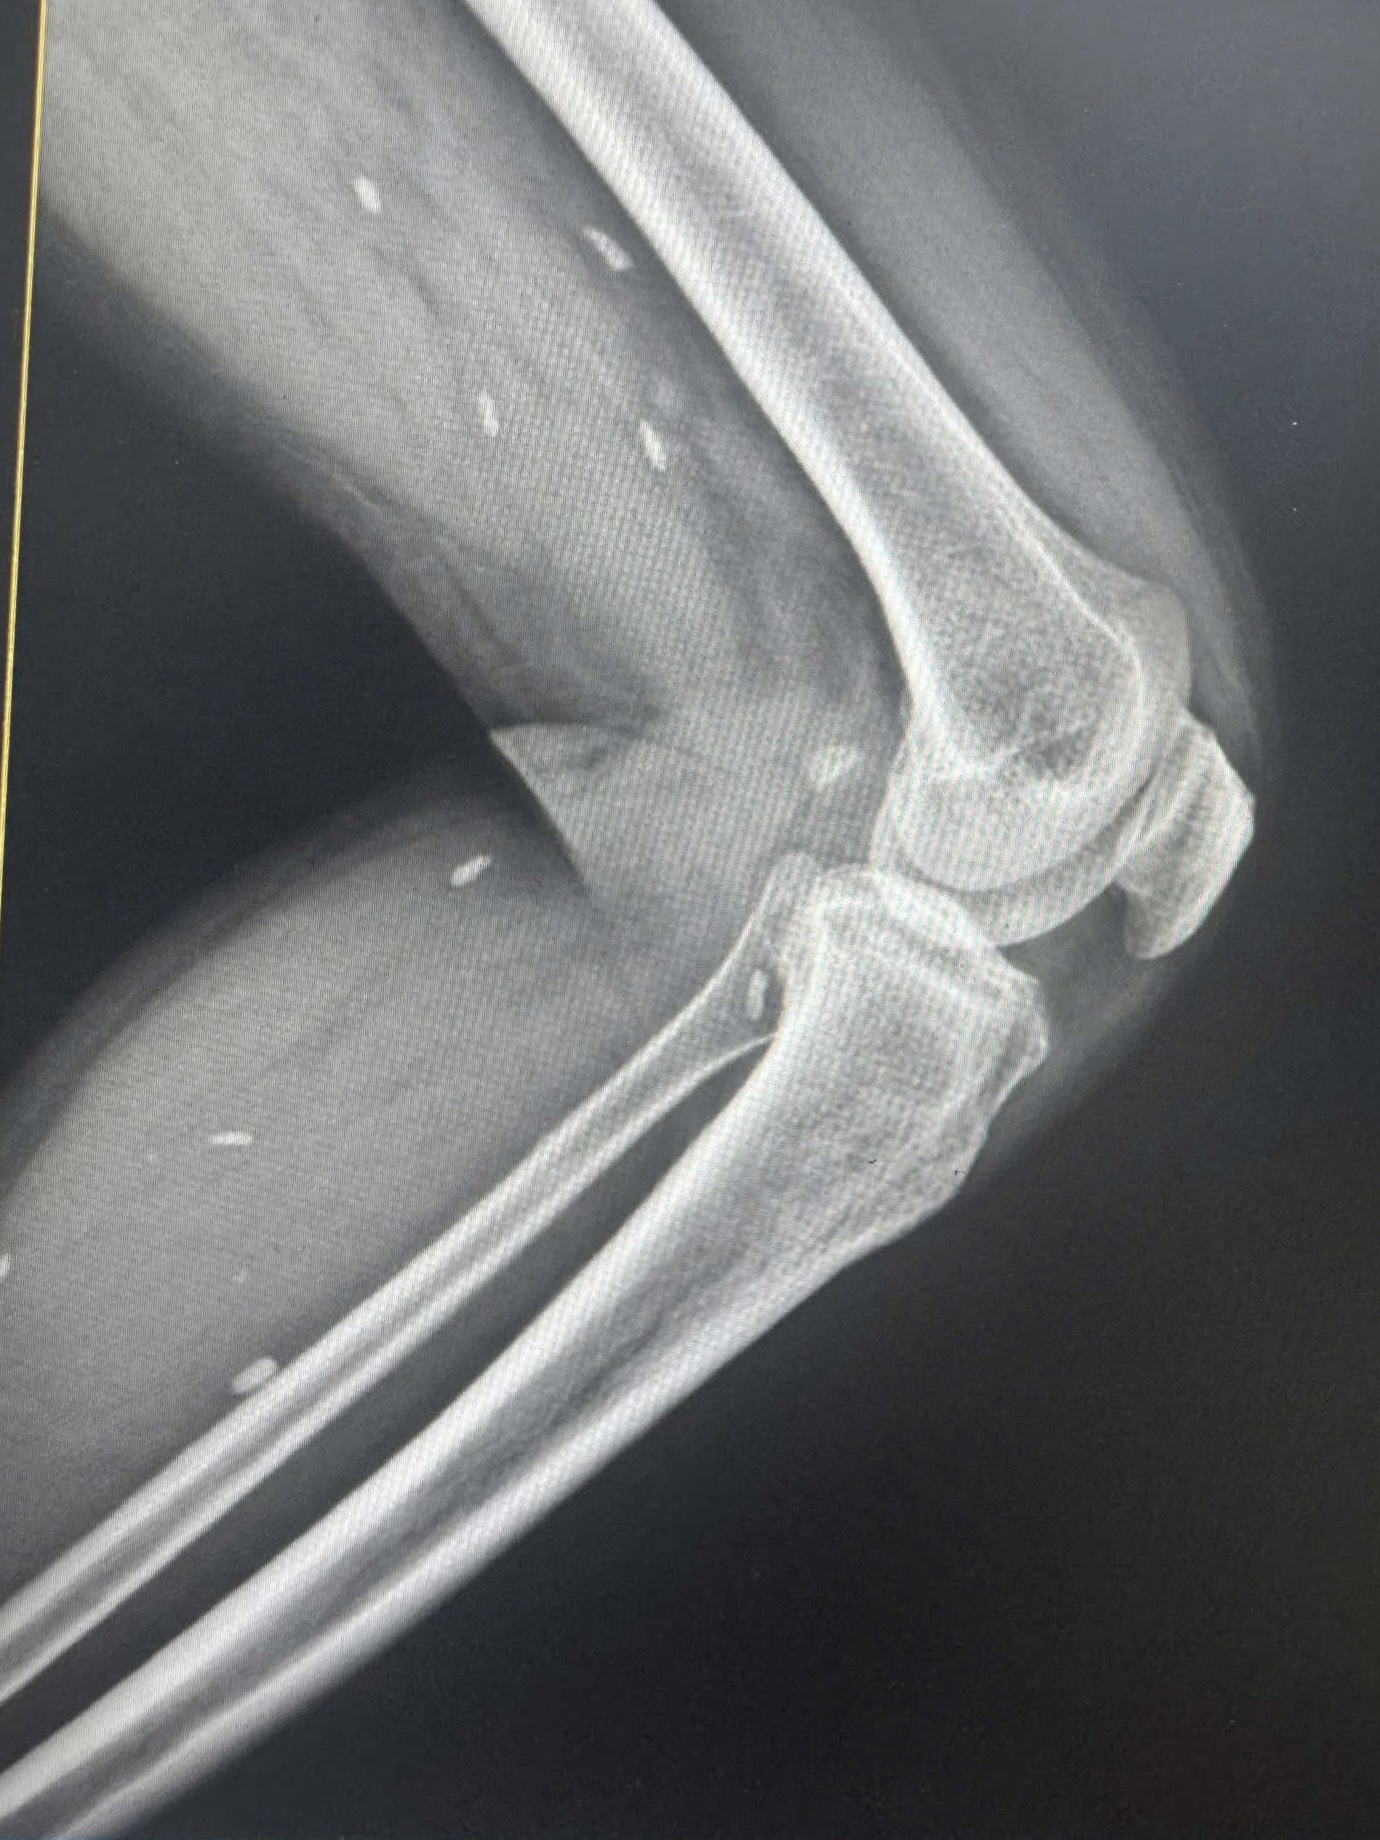

Nhiều kén sán kích thước như hạt gạo nằm rải rác ở các mô vùng xương đùi và cẳng chân bệnh nhân.

Người bệnh đến thăm khám khi có triệu chứng mệt mỏi, đau nhức nhiều ở vùng chân, lưng, hạn chế vận động… Bệnh nhân được chỉ định thực hiện chụp X- quang thường quy.

Bác sĩ Đỗ Hồng Thanh, Phó Giám đốc Trung tâm Y tế khu vực Thạch Hãn chia sẻ với Sức khỏe & Đời sống, kết quả X – quang phát hiện nhiều kén sán kích thước như hạt gạo nằm rải rác ở các mô vùng xương đùi và cẳng chân bệnh nhân.